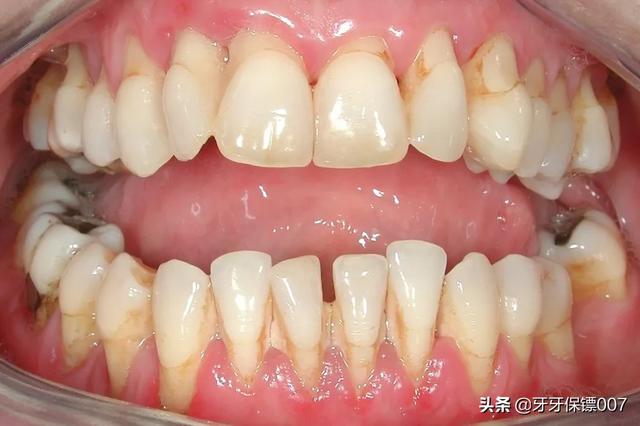

下牙大部分松动了,排除外伤因素,那么大概率是患上了牙周炎。牙周炎的牙齿,牙槽骨发生吸收,牙龈炎症明显,严重时甚至发生牙周袋溢脓,牙齿明显松动。此外,炎症波及牙根周围时,会引起逆行性牙髓炎,导致明显的冷热刺激痛。

02.牙周炎有什么表现

牙周炎的表现,有多种多样,常见的临床症状以下几种。

• 牙龈炎症

牙齿周围炎症明显,往往伴有增生、明显红肿等情况,进食时可能有出血等情况,严重时牙周袋会有脓液渗出,甚至引起急性牙周脓肿,带来明显的疼痛不适。

• 牙齿松动

牙齿松动,这是很多牙周炎患者就诊的主要原因。松动是因为牙槽骨发生吸收,牙齿失去扶持作用而松动。